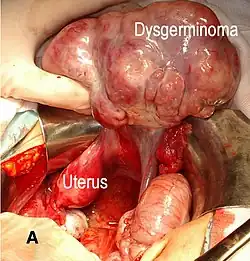

Dysgerminoma

Dysgerminoma accounts for 35% of ovarian cancer in young women and is the most likely germ cell tumor to metastasize to the lymph nodes; nodal metastases occur in 25–30% of cases.[33][32] These tumors may have mutations in the KIT gene, a mutation known for its role in gastrointestinal stromal tumor. People with an XY karyotype and ovaries (gonadal dysgenesis) or an X,0 karyotype and ovaries (Turner syndrome) who develop a unilateral dysgerminoma are at risk for a gonadoblastoma in the other ovary, and in this case, both ovaries are usually removed when a unilateral dysgerminoma is discovered to avoid the risk of another malignant tumor. Gonadoblastomas in people with Swyer or Turner syndrome become malignant in approximately 40% of cases. However, in general, dysgerminomas are bilateral 10–20% of the time.[26][32]

They are composed of cells that cannot differentiate further and develop directly from germ cells or from gonadoblastomas. Dysgerminomas contain syncytiotrophoblasts in approximately 5% of cases, and can therefore cause elevated hCG levels. On gross appearance, dysgerminomas are typically pink to tan-colored, have multiple lobes, and are solid. Microscopically, they appear identical to seminomas and very close to embryonic primordial germ cells, having large, polyhedral, rounded clear cells. The nuclei are uniform and round or square with prominent nucleoli and the cytoplasm has high levels of glycogen. Inflammation is another prominent histologic feature of dysgerminomas.[32]